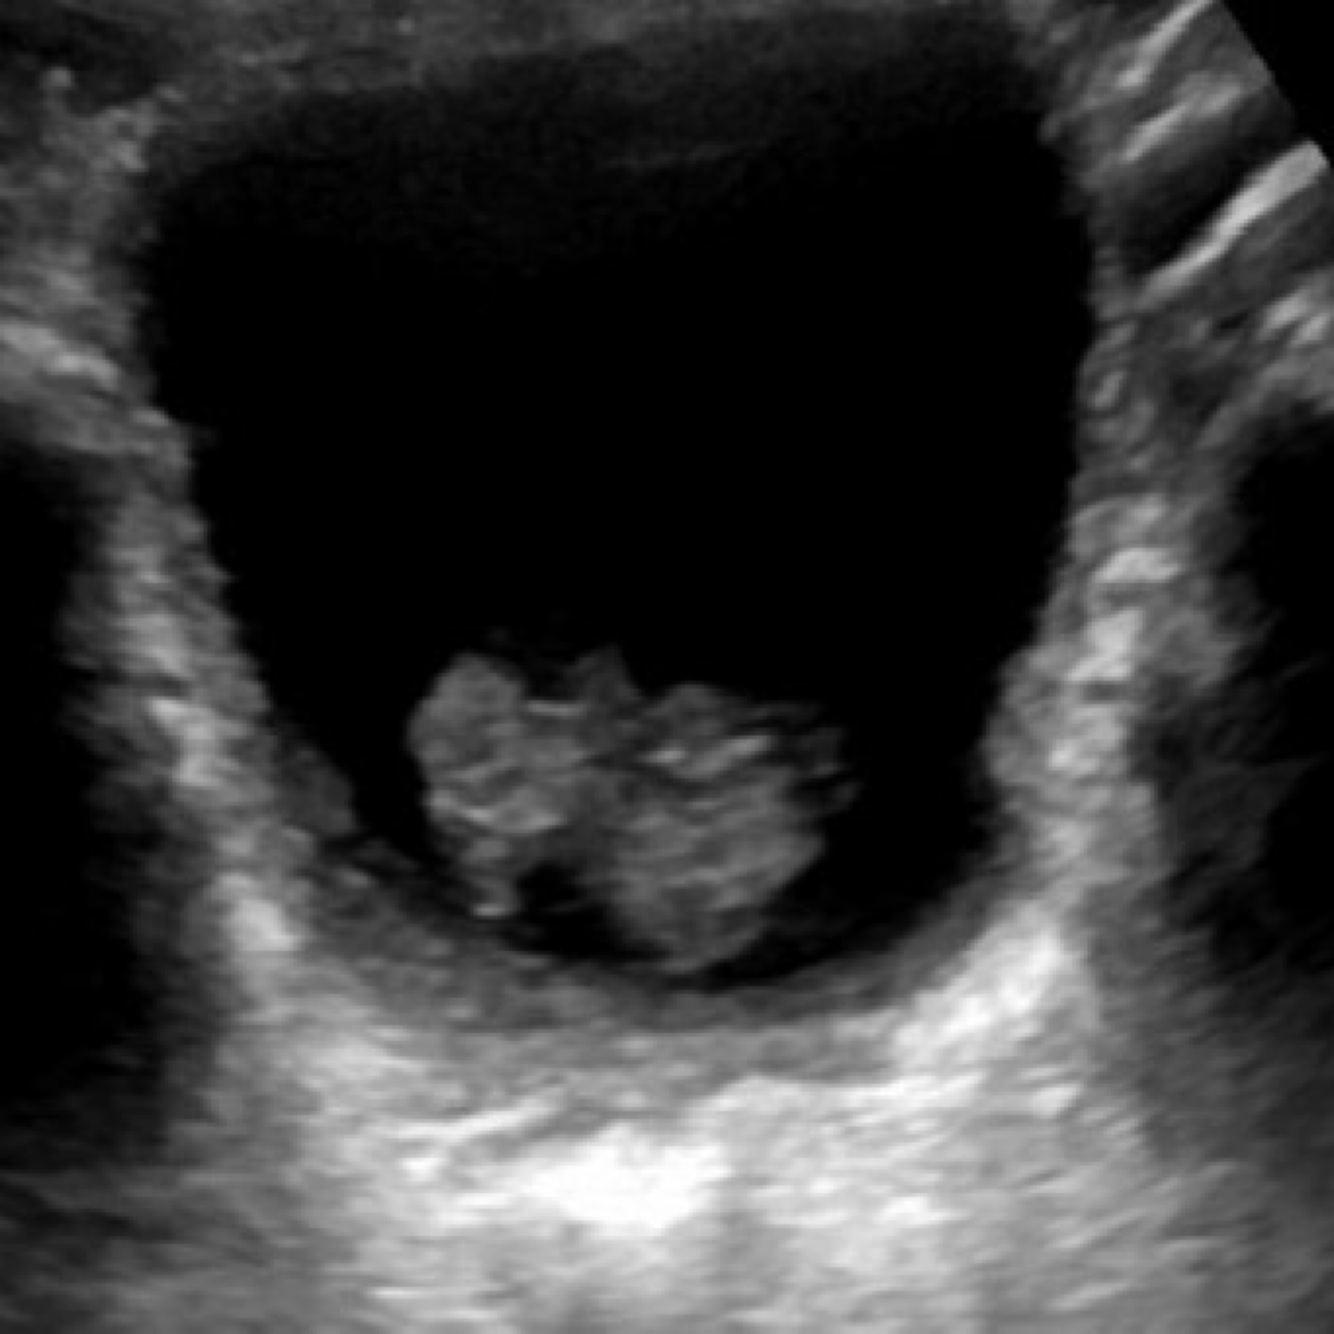

Most common urinary tract malignancy in pediatric population aka sarcoma botryoides

–Highest incidence at 4 to 5 years

–Highest incidence in males (1.6 males:1 females)

Sonographic appearance

–Solid mass, homogeneous with muscle like appearance

–Anechoic foci caused by necrosis or hemorrhage

–Can originated from the bladder/prostate in males and from the bladder/vagina/cx in females

–Presents with urinary tract obstruction or hematuria

Rhabdomyosarcoma of the bladder